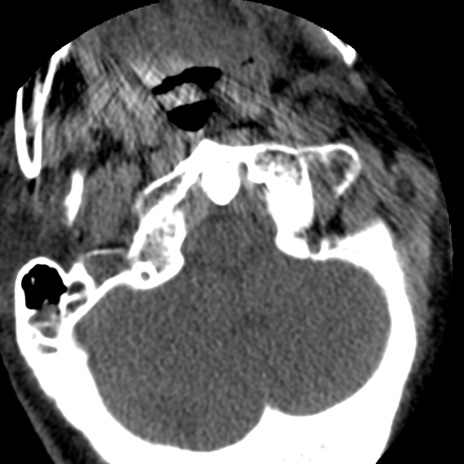

症例50 頚椎CT(横断像)

冠状断像